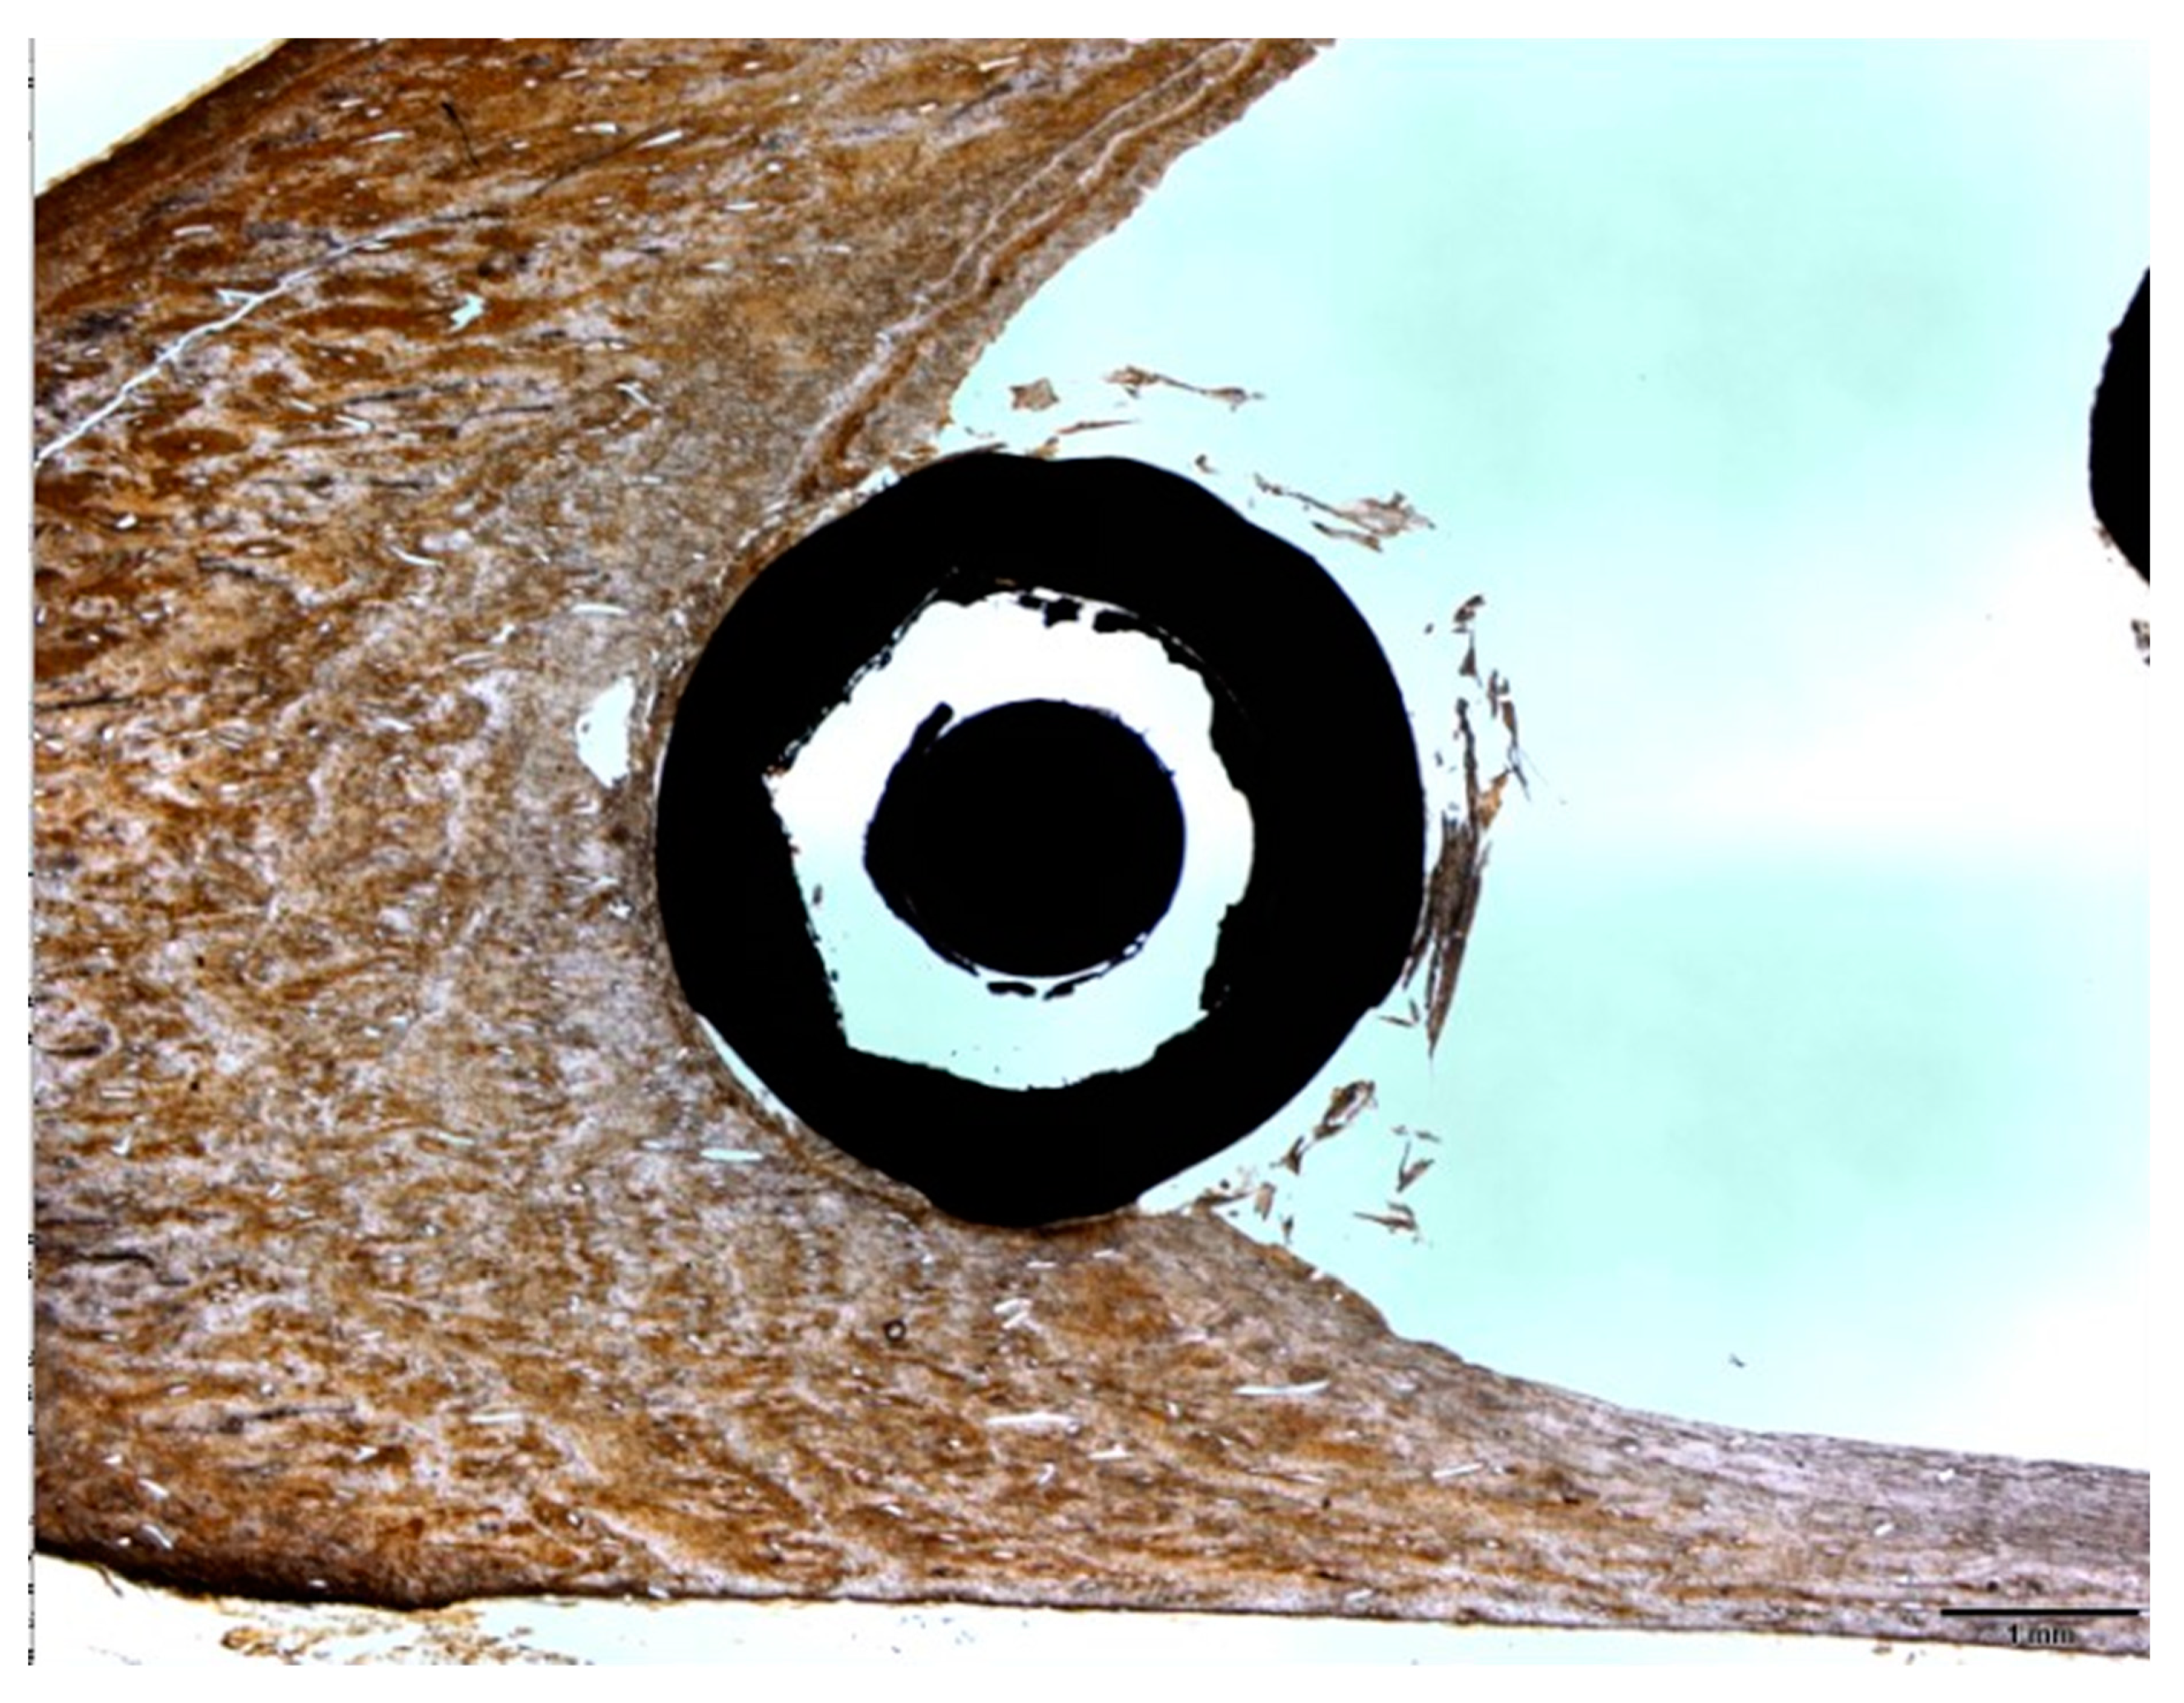

2.6. Histomorphometric Analysis

3.3. Experimental Animal Study